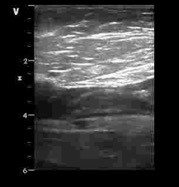

В статье представлен случай успешного хирургического лечения тромбоэмболии легочной артерии у пациентки с высоким риском ранней сердечной смерти на фоне парадоксальной эмболии, осложненной острым нарушением мозгового кровообращения. Криптогенное острое нарушение мозгового кровообращения в комбинации с тяжелой прогрессирующей правожелудочковой недостаточностью на фоне ТЭЛА обусловливает серьезные трудности при принятии решения в отношении тактики лечения у данных больных. Внутрисердечная локализация тромбоэмбола, угрожаемая развитием не только рецидива тромбоэмболии легочной артерии, но и парадоксальной эмболии требует незамедлительного выполнения комплекса дифференциально-диагностического обследования, направленного на верификацию патофизиологического механизма развития заболевания, что во многом определяет эффективность проводимого лечения. Анализ доступных литературных данных, приведенный в работе, а также анализ клинического случая позволяют выработать тактический алгоритм в этой группе пациентов и определить показания к открытому оперативному вмешательству.

Гамзаев А.Б., Федоров С.А., Чигинев В.А., Пичугин В.В., Теплицкая В.В., Сухова М.Б., Пименова П.В., Домнин С.Е. Хирургическое лечение тромбоэмболии легочной артерии высокого риска на фоне парадоксальной эмболии, осложненной острым нарушением мозгового кровообращения. Вестник хирургии имени И.И. Грекова. 2022;181(3):69-75. https://doi.org/10.24884/0042-4625-2022-181-3-69-75

Gamzaev A.B., Fedorov S.A., Chiginev V.A., Pichugin V.V., Teplitskaya V.V., Sukhova M.B., Pimenova P.V., Domnin S.E. Surgical treatment of high-risk pulmonary embolism associated with paradoxical embolism, complicated by acute cerebrovascular accident. Grekov's Bulletin of Surgery. 2022;181(3):69-75. (In Russ.) https://doi.org/10.24884/0042-4625-2022-181-3-69-75